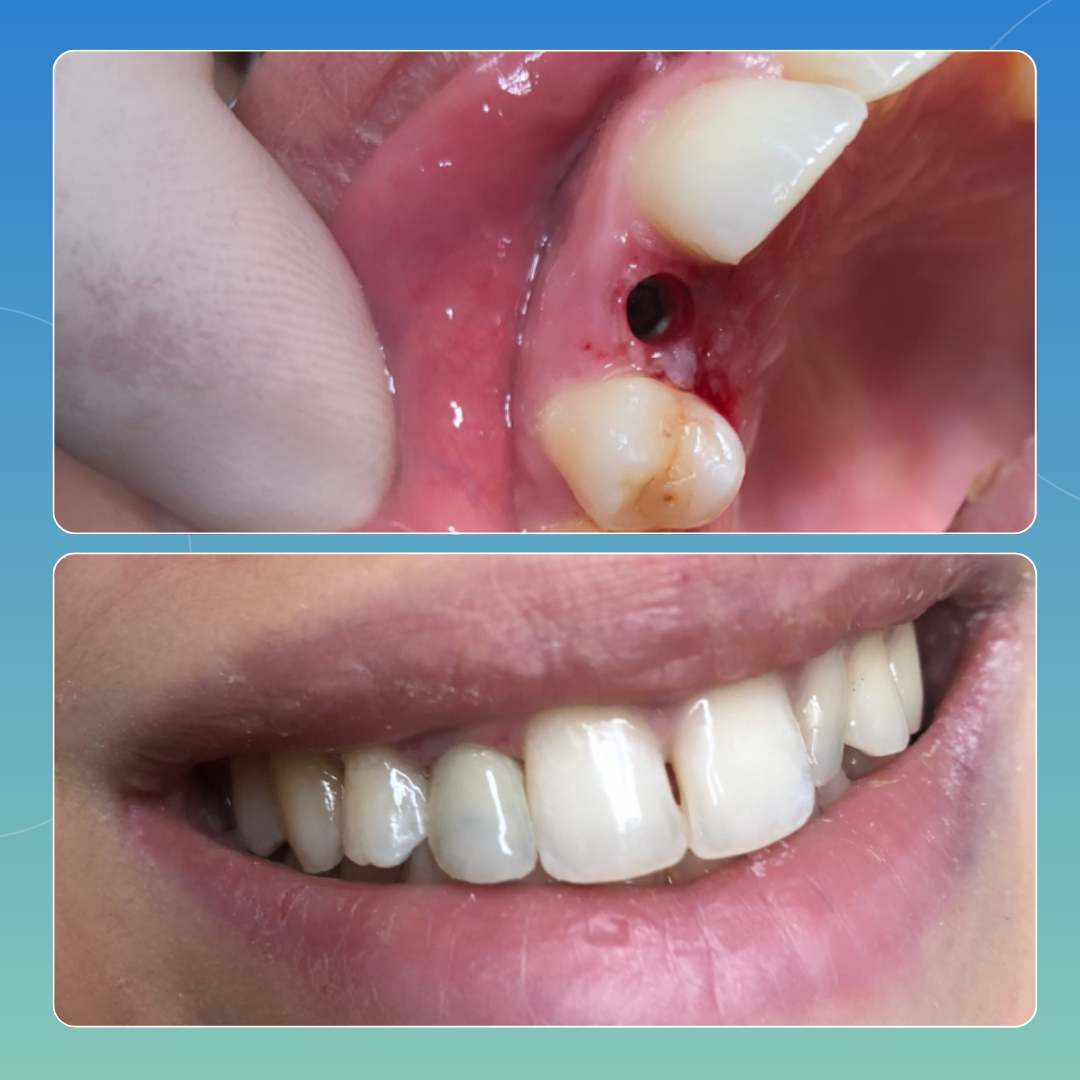

CASI CLINICI

Approccio personalizzato, esiti documentati

Di seguito riportiamo casi analizzati e svolti all’interno del nostro poliambulatorio che pensiamo possano rendere a pieno ciò che è per noi il nostro lavoro: passione e attenzione ai dettagli, volendo sempre il risultato migliore possibile che possa dar contentezza al paziente e a noi stessi